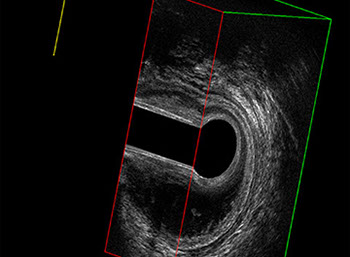

L’ecografia transanale è un esame diagnostico per immagini che consiste nell’introduzione di un trasduttore ad ultrasuoni. Le immagini qualitativamente migliori del canale anale sono ottenute usando un trasduttore rotante, montato in un manipolo rigido, che fornisce un’immagine a 360°. Con le apparecchiature più moderne è anche possibile ottenere immagini tridimensionali.

Proctal dispone di apparecchiatura per ecografia endoanale 3D con sonda rotante.

Sezione Longitudinale 3D con Tramite Fistoloso Intersfinterico Basso Anteriore Semplice